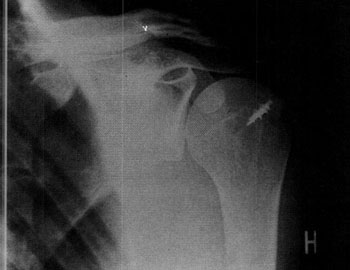

Figura II:

Déficit en la abducción activa.

Maniobra de debilidad o falta de fuerza.